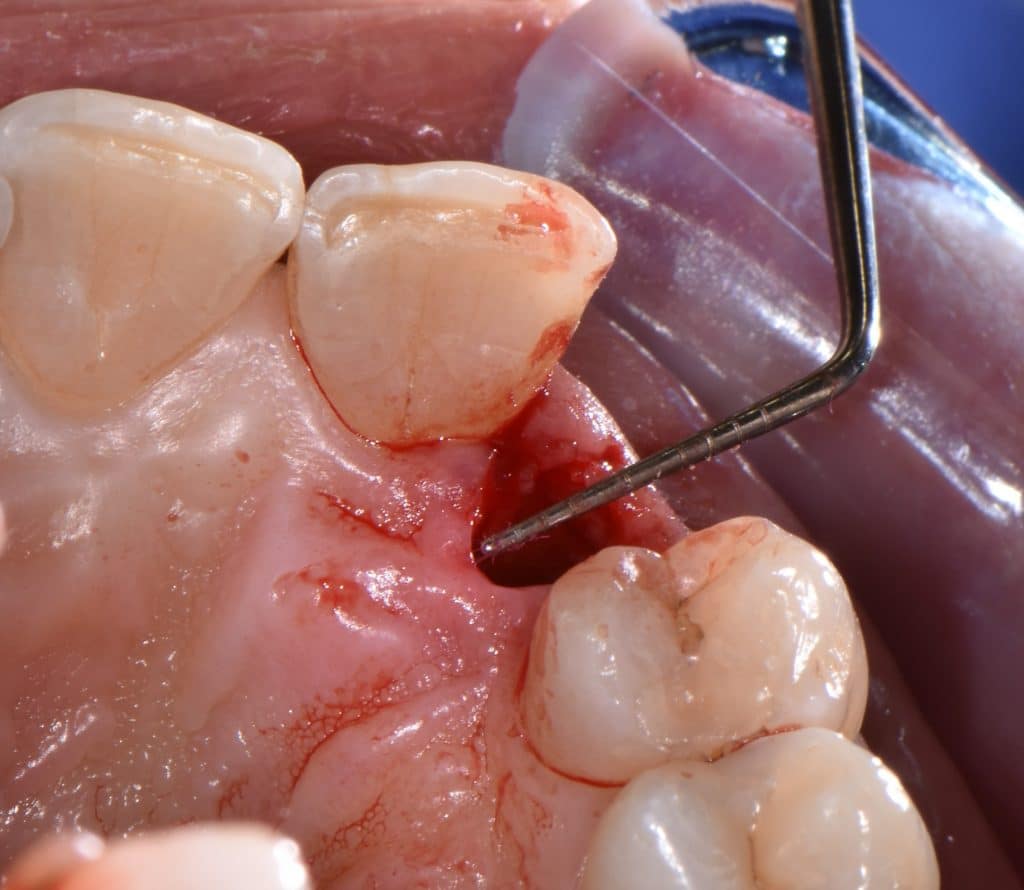

La pz N.G. di anni 52 (ASA 1) viene visitata nel mese di settembre 2017 per la mobilità ed inestetismo dell’elemento protesico 22, (foto iniziali sequenza 1) si evidenzia una frattura parziale della radice, si decide per l’estrazione ( foto sequenza 2) e sostituzione dell’elemento con un restauro implanto-protesico. Purtroppo la scarsa quota ossea apicale all’alveolo post-estrattivo (foto 2 rx) e l’alta valenza estetica dell’elemento ci rende cauti e si programma una socket preservation post estrattiva con l’ausilio delle membrane di prf (foto prf e socket sequenza 3 e 4). Durente i 5 mesi di guarigione la pz porta una protesi parziale mobile (foto 5,2) , a guarigione del sito post estrattivo si evidenzia una buona conservazione dei volumi osseo-gengivali,(foto guarigione sequenza 6) se pur presente una recessione distale all’elemnto 21.Nel mese di febbraio 2018 si procede all’inserimento di un impianto max-stability 3,75x12mm disegnando un lembo anticipato palatino per consentire un aumento dei tessuti vestibolari suturando con tecnica rool flap e trasformando l’elemento parziale mobile in una corona singola a carico immediato sul moncone temporameo applicando i concetti protesici bopt , (foto impianto moncone protesi provvisoria sequenza foto 7-8-9). Durante il periodo di maturazione dei tessuti molli vengono apportate opportune modifiche ai profili del provvisorio al fine di dare maggior spazio al tessuto gengivale, ( fotosequenza 10).Dopo circa 2 mesi dal protesizzazione provvisoria si è proceduto alla realizzazione del manufatto protesico con tecnica chair side sirona con l’ausilio del t-base (foto sequenza 11-12-13), realizzando in una sola seduta una corona in disilicato, ottenendo un risultato più che soddisfacente (Foto 14). Nel controllo a 3 mesi dal carico definitivo si apprezza la perfetta conservazione dei livelli ossei e gengivali. (foto sequenza 15).concludo con un follow up a 18 . Tengo a sottolineare che un caso come questo è stato conducibile con buoni risultati solo grazie alla piena fiducia della pz e alla sua massima motivazione e collaborazione. Ad oggi la pz sorride soddisfatta del risultato. E questo rappresenta la massima ricompensa di chi dedica tutto se stesso alla professione.